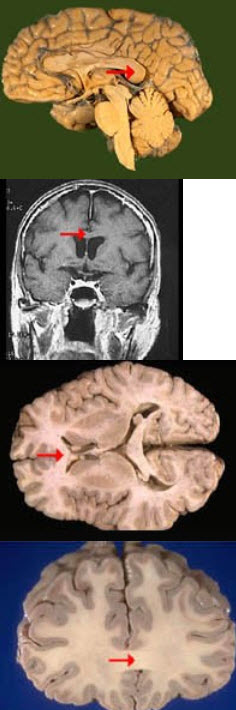

如图箭头所示为大脑哪个部位( )

A:前连合

B:胼胝体

C:透明隔

D:穹窿

E:中脑导水管